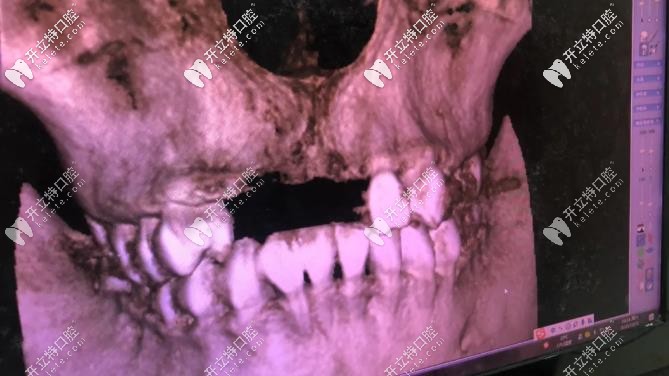

▼這個(gè)全景影像檢查可快,幾分鐘就出來▼

全景影像檢查可快,幾分鐘就出來

由于我長(zhǎng)期帶假牙,牙骨頭薄,后期種牙手術(shù)難度較大;唯美口腔:彭參醫(yī)師在牙齒缺失修復(fù)、復(fù)雜種植這方面很擅長(zhǎng),就找的他,(我家人目標(biāo)很明確的,對(duì)癥下藥)。

1年多點(diǎn)完成種植,之前缺牙時(shí)間長(zhǎng),再加上長(zhǎng)期戴假牙,彭醫(yī)生:說我的骨頭比較?。ㄕ7N牙厚度:6.5-7毫米,我骨厚度就:3毫米),所以要增量骨組織;我是四顆門牙缺失,種2顆植體,然后戴四連冠就好;現(xiàn)在明白,做種植牙,并不是缺幾顆種植牙幾顆。